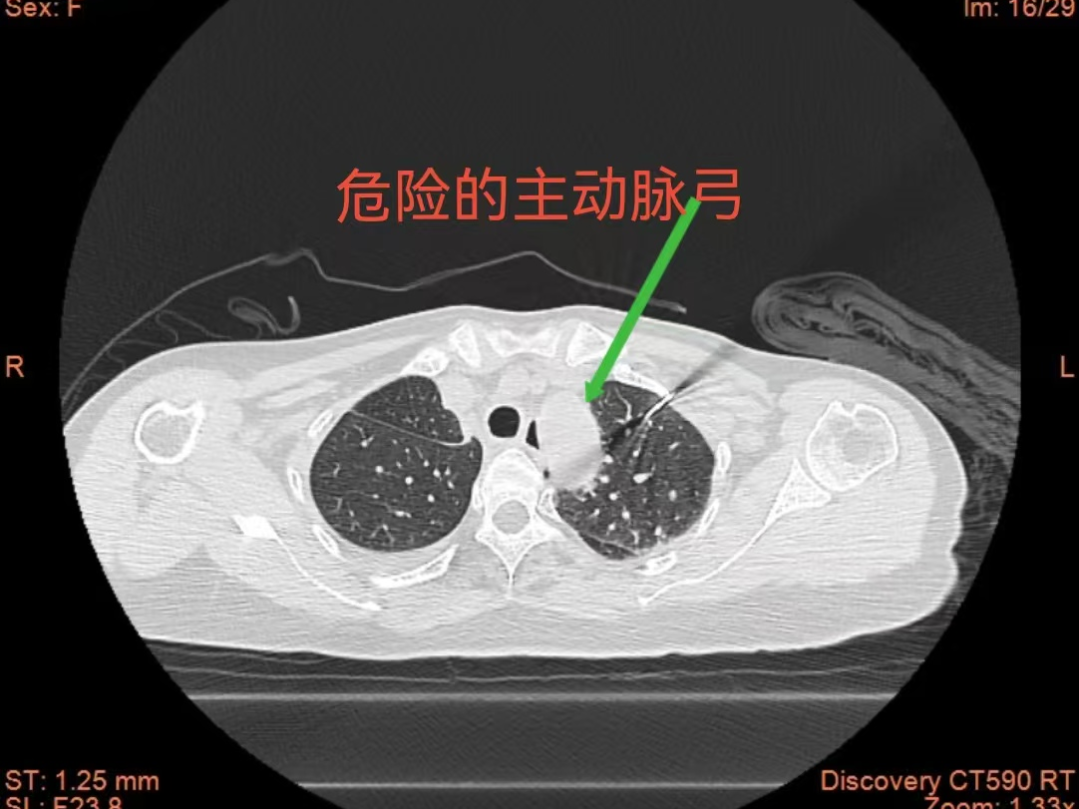

患者因右肺两处高危结节入院,已由我院胸心血管外科团队顺利完成手术切除,术后复查CT提示:左肺主动脉弓旁高危结节。此位置极其凶险,紧邻主动脉弓,术中极易损伤大血管,手术风险极高。

面对这一临床难题,呼吸与危重症医学科副主任王开金副主任医师组织团队通过充分评估,决定采用CT引导下经皮肺结节微波消融术,并创新性运用人工气胸+液体隔离技术。